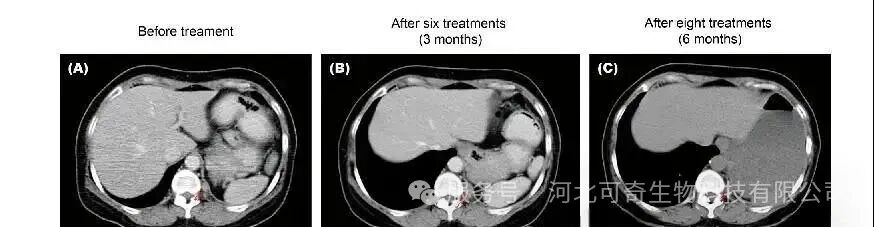

同种异体 Vγ9Vδ2 T 细胞的临床研究尤为亮眼。一项纳入 132 例晚期癌症患者的试验显示,多次接受细胞输注的患者生存期显著延长,肝癌患者平均生存 23.1 个月,肺癌患者 19.1 个月,远超常规治疗预期。